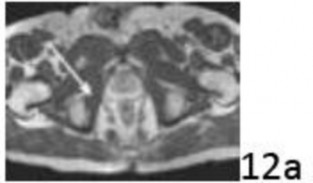

10. # 12a Figure 12a shows a cross section of the pelvis at the level of the greater trochanters. What structure is marked with the arrow?

DISCUSSION: In Figure 12b, the arrow marks the obturator internus muscle which projects posteriorly and banks around the ischium, inserting on the posterior aspect of the proximal femur, just below the piriformis. The other structures are labeled. The obturator externus is more anterior and is seen anterior to the ischium. The adductor magnus is not seen in this image, and is more distal. The adductor longus is just starting to appear anteriorly (with the adductor brevis just posterior), and the pectineus is seen posterior and just deep to the femoral vessels. The Preferred Response to Ques# 12 is 2.